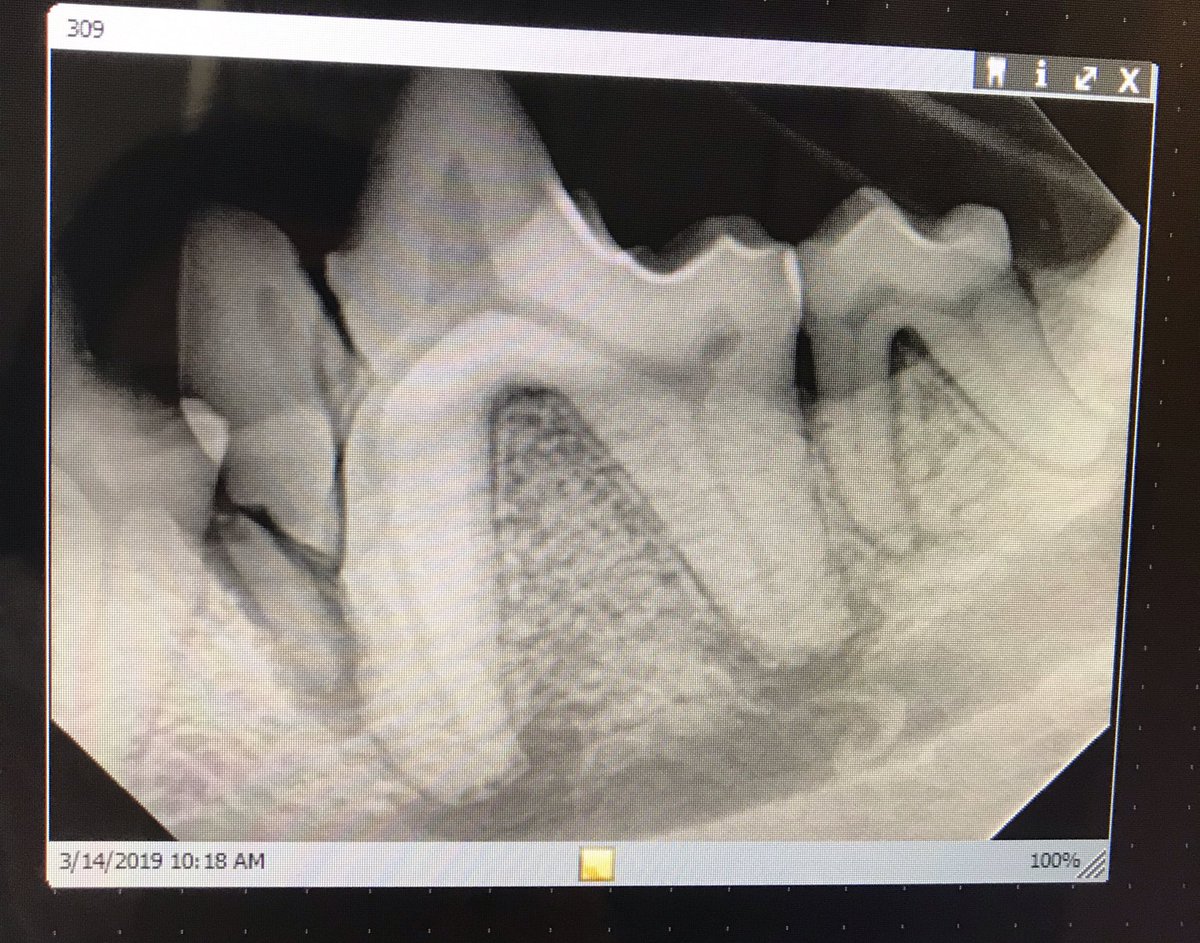

Interesting #dental case: here’s the dental X-ray. There’s the fracture, infected slab of broken tooth root, #periapical lysis. This tooth was extracted.